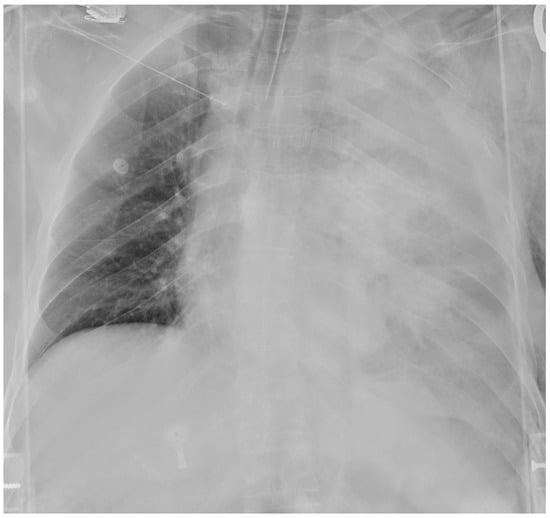

The postoperative course took place in the Intensive Care unit for nine days, during which the patient received blood transfusions (2 units), vasopressor support, antibiotic therapy and steroids. Bronchial toilet was performed twice to free of blood and secretions the tracheobronchial tree. Due to the occurrence of a fever and a rise in the inflammation markers a CT scan was ordered on p.o. day 3, showing an intraparenchymal hematoma (6 cm) in the left upper lobe (LUL), without active bleeding spots (Figure 2A). A conservative approach was chosen and the fever progressively subsided, blood tests gradually normalized and the hematoma progressively shrunk (Figure 2B). The patient returned to the ward on the 9th p.o. day and was discharged from the hospital on p.o. day 20. A chest film obtained a month later revealed almost complete reabsorption of the hematoma, with a very satisfactory lung re-expansion (Figure 3). Data regarding preoperative parameters, intraoperative steps and postoperative events are reported in Table 1.

Figure 2. Postoperative sequential chest CT scans showing parenchymal LUL hematoma (A) and initial shrinking at CT follow-up (B).